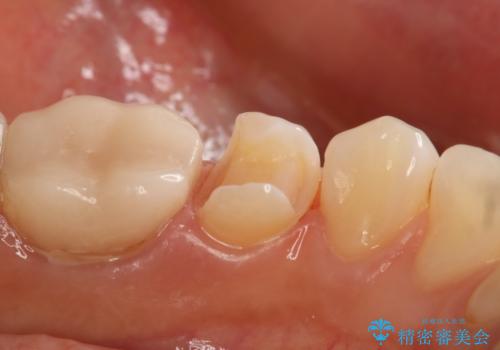

銀歯を白くしたい セラミックインレー

- 左下5番の銀歯をセラミックにやり変え希望の患者様です。

切削量を考慮し、セラミックインレーでの治療を選択しました。

銀歯直下のう蝕を除去しCRで裏層を行った上で、形成・印象を行っています。